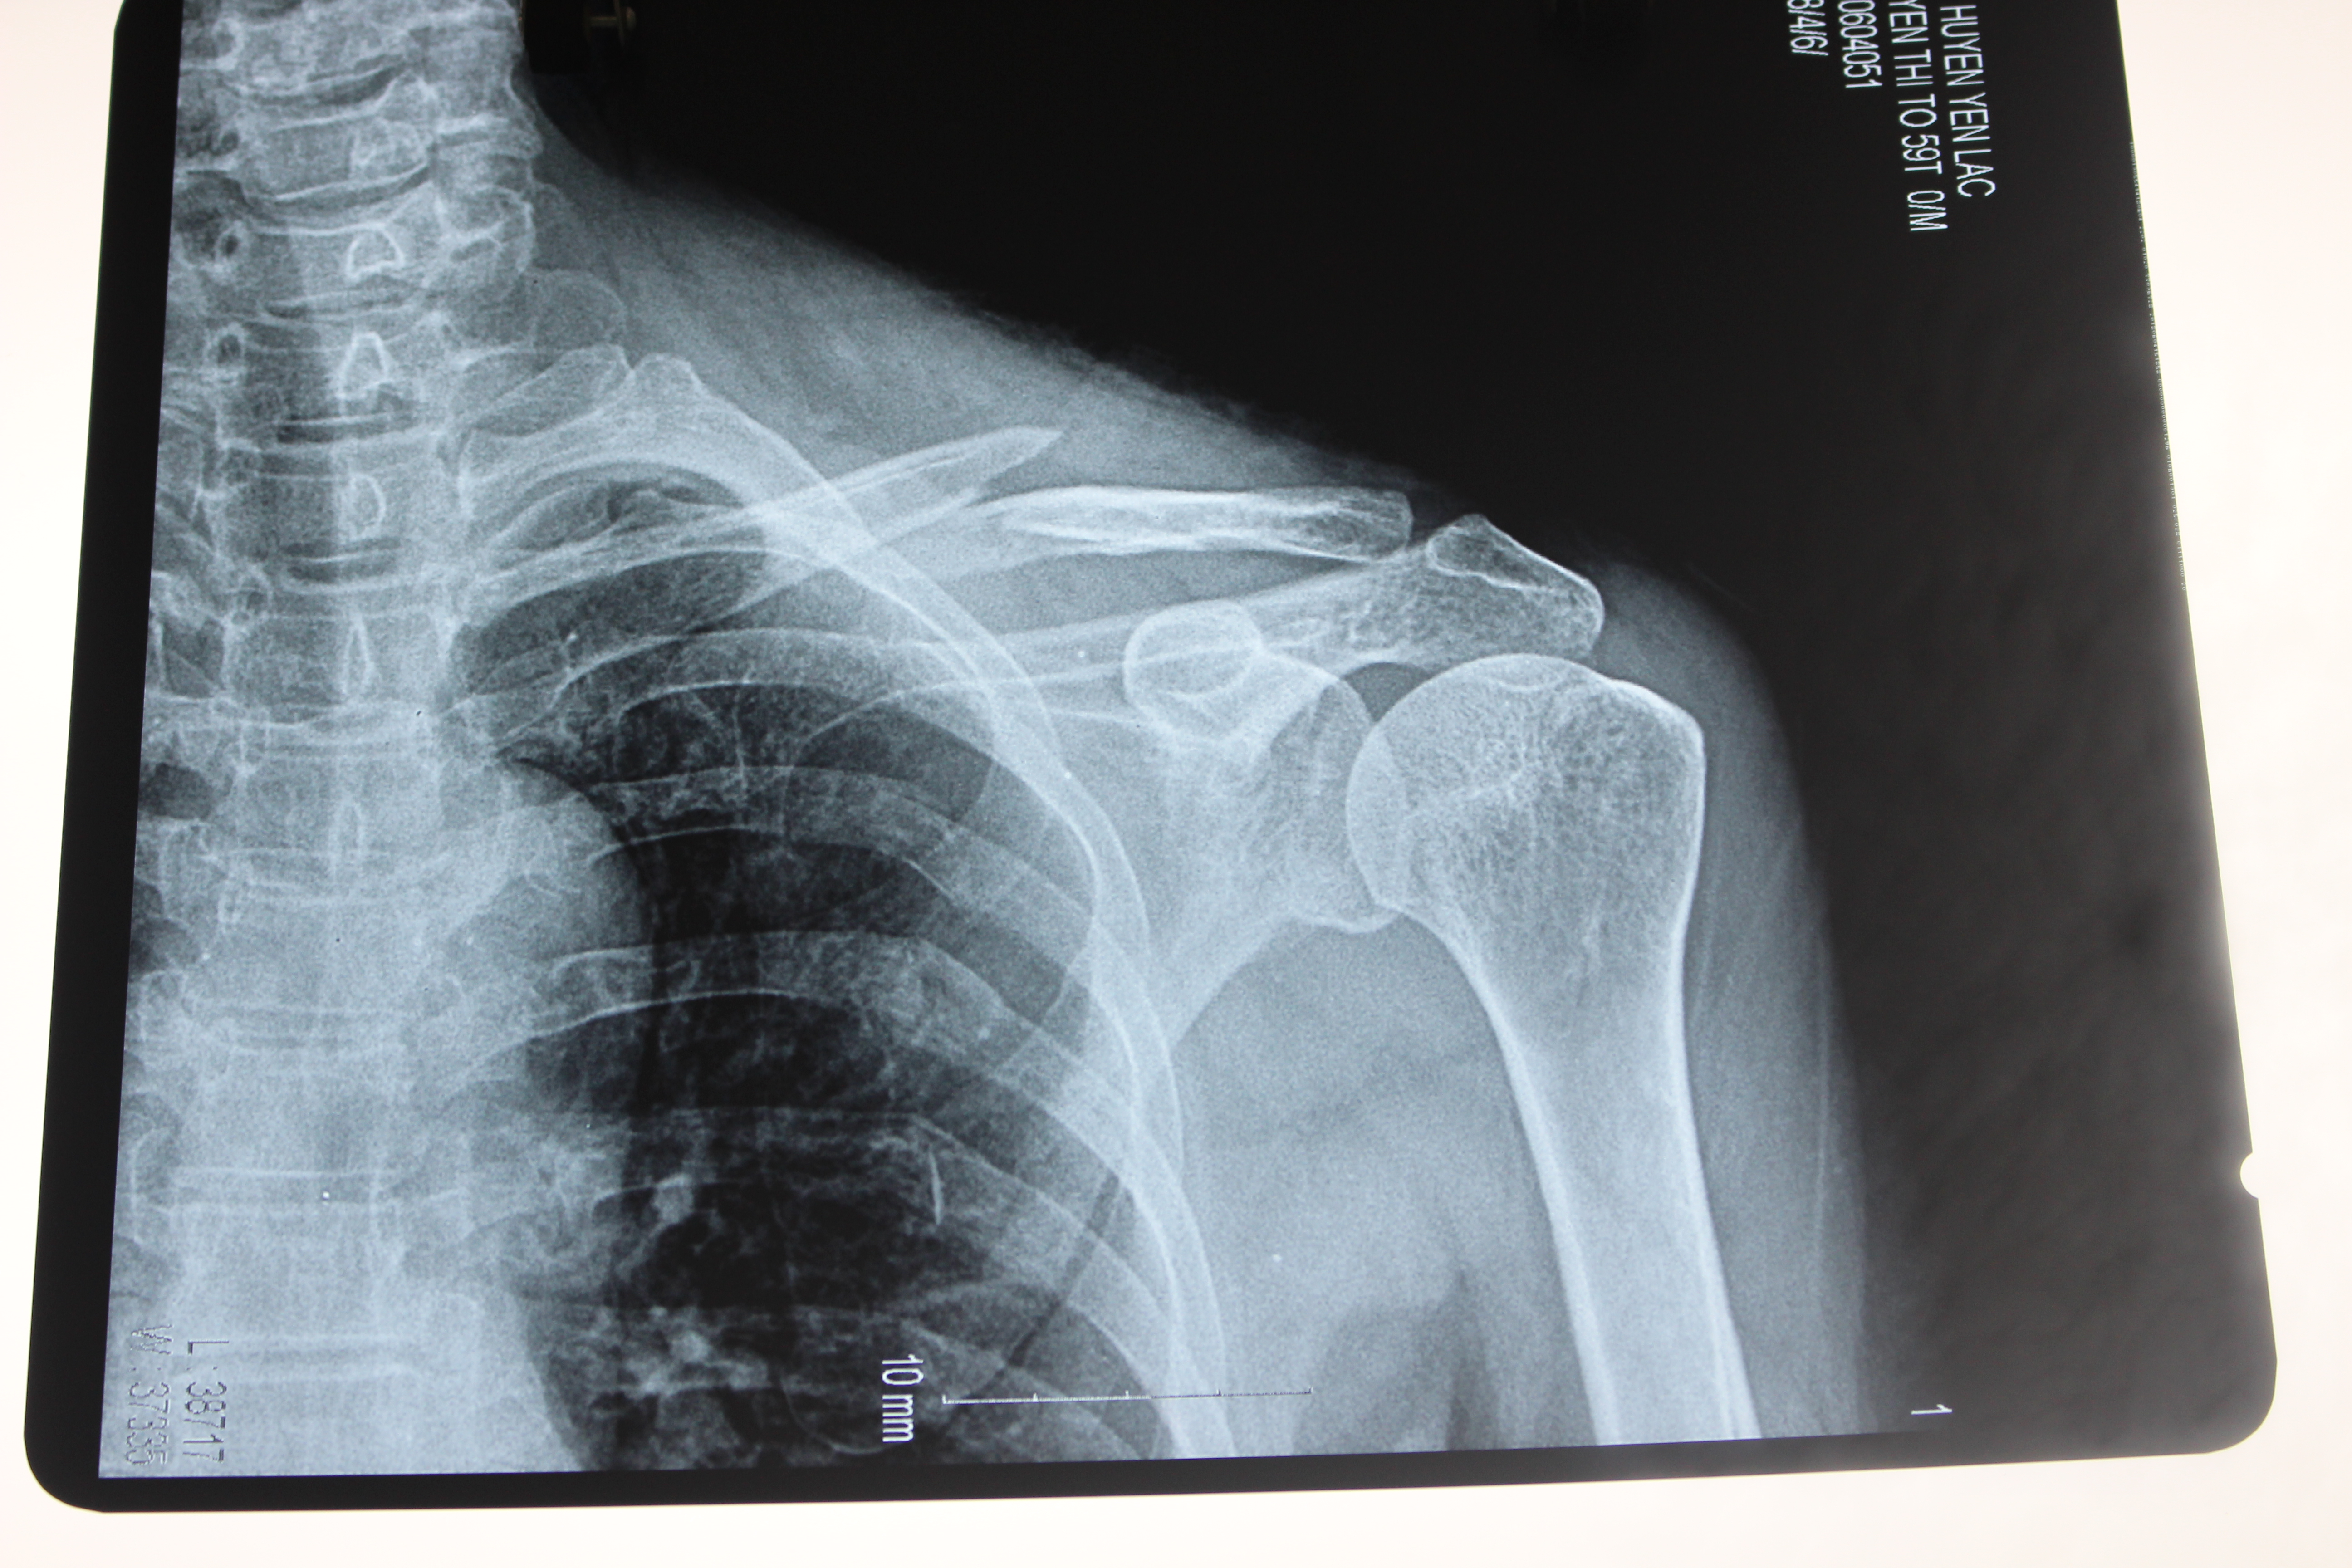

Chiều ngày 5 tháng 6 năm 2016. Tại khoa ngoại tổng hợp gây mê hồi sức- Trung tâm y tế huyện Yên Lạc. Bác sỹ CKI Nguyễn Hoàng Phương cùng ê kíp đã tiến hành phẫu thuật kết hợp xương đòn trái cho bệnh nhân nữ 59 tuổi – Thôn Nho Lẻ – xã Tam Hồng – Huyện Yên Lạc – tỉnh Vĩnh Phúc. Bệnh nhân vào viện với lý do đau vai trái, hạn chế vận động, sau một tai nạn giao thông, kèm theo tiền sử tăng huyết áp đã điều trị nhiều năm. Qua thăm khám và kết quả chụp Xquang cho thấy hình ảnh gẫy 1/3 giữa xương đòn trái. Sau khi tư vấn kỹ cho bệnh nhân và gia đình, bệnh nhân đã được các bác sỹ tiến hành phẫu thuật kết hợp xương đòn trái, sau phẫu thuật bệnh nhân ổn định, đỡ đau nhiều, sức khỏe tiến triển tốt.

Một số hình ảnh phẫu thuật kết hợp xương đòn trái.